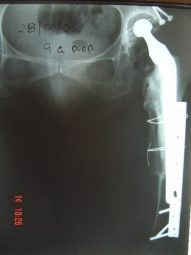

Revisión de prótesis con injerto óseo masivo

Envíado por Dr. Ricardo Antonio Gómez G.